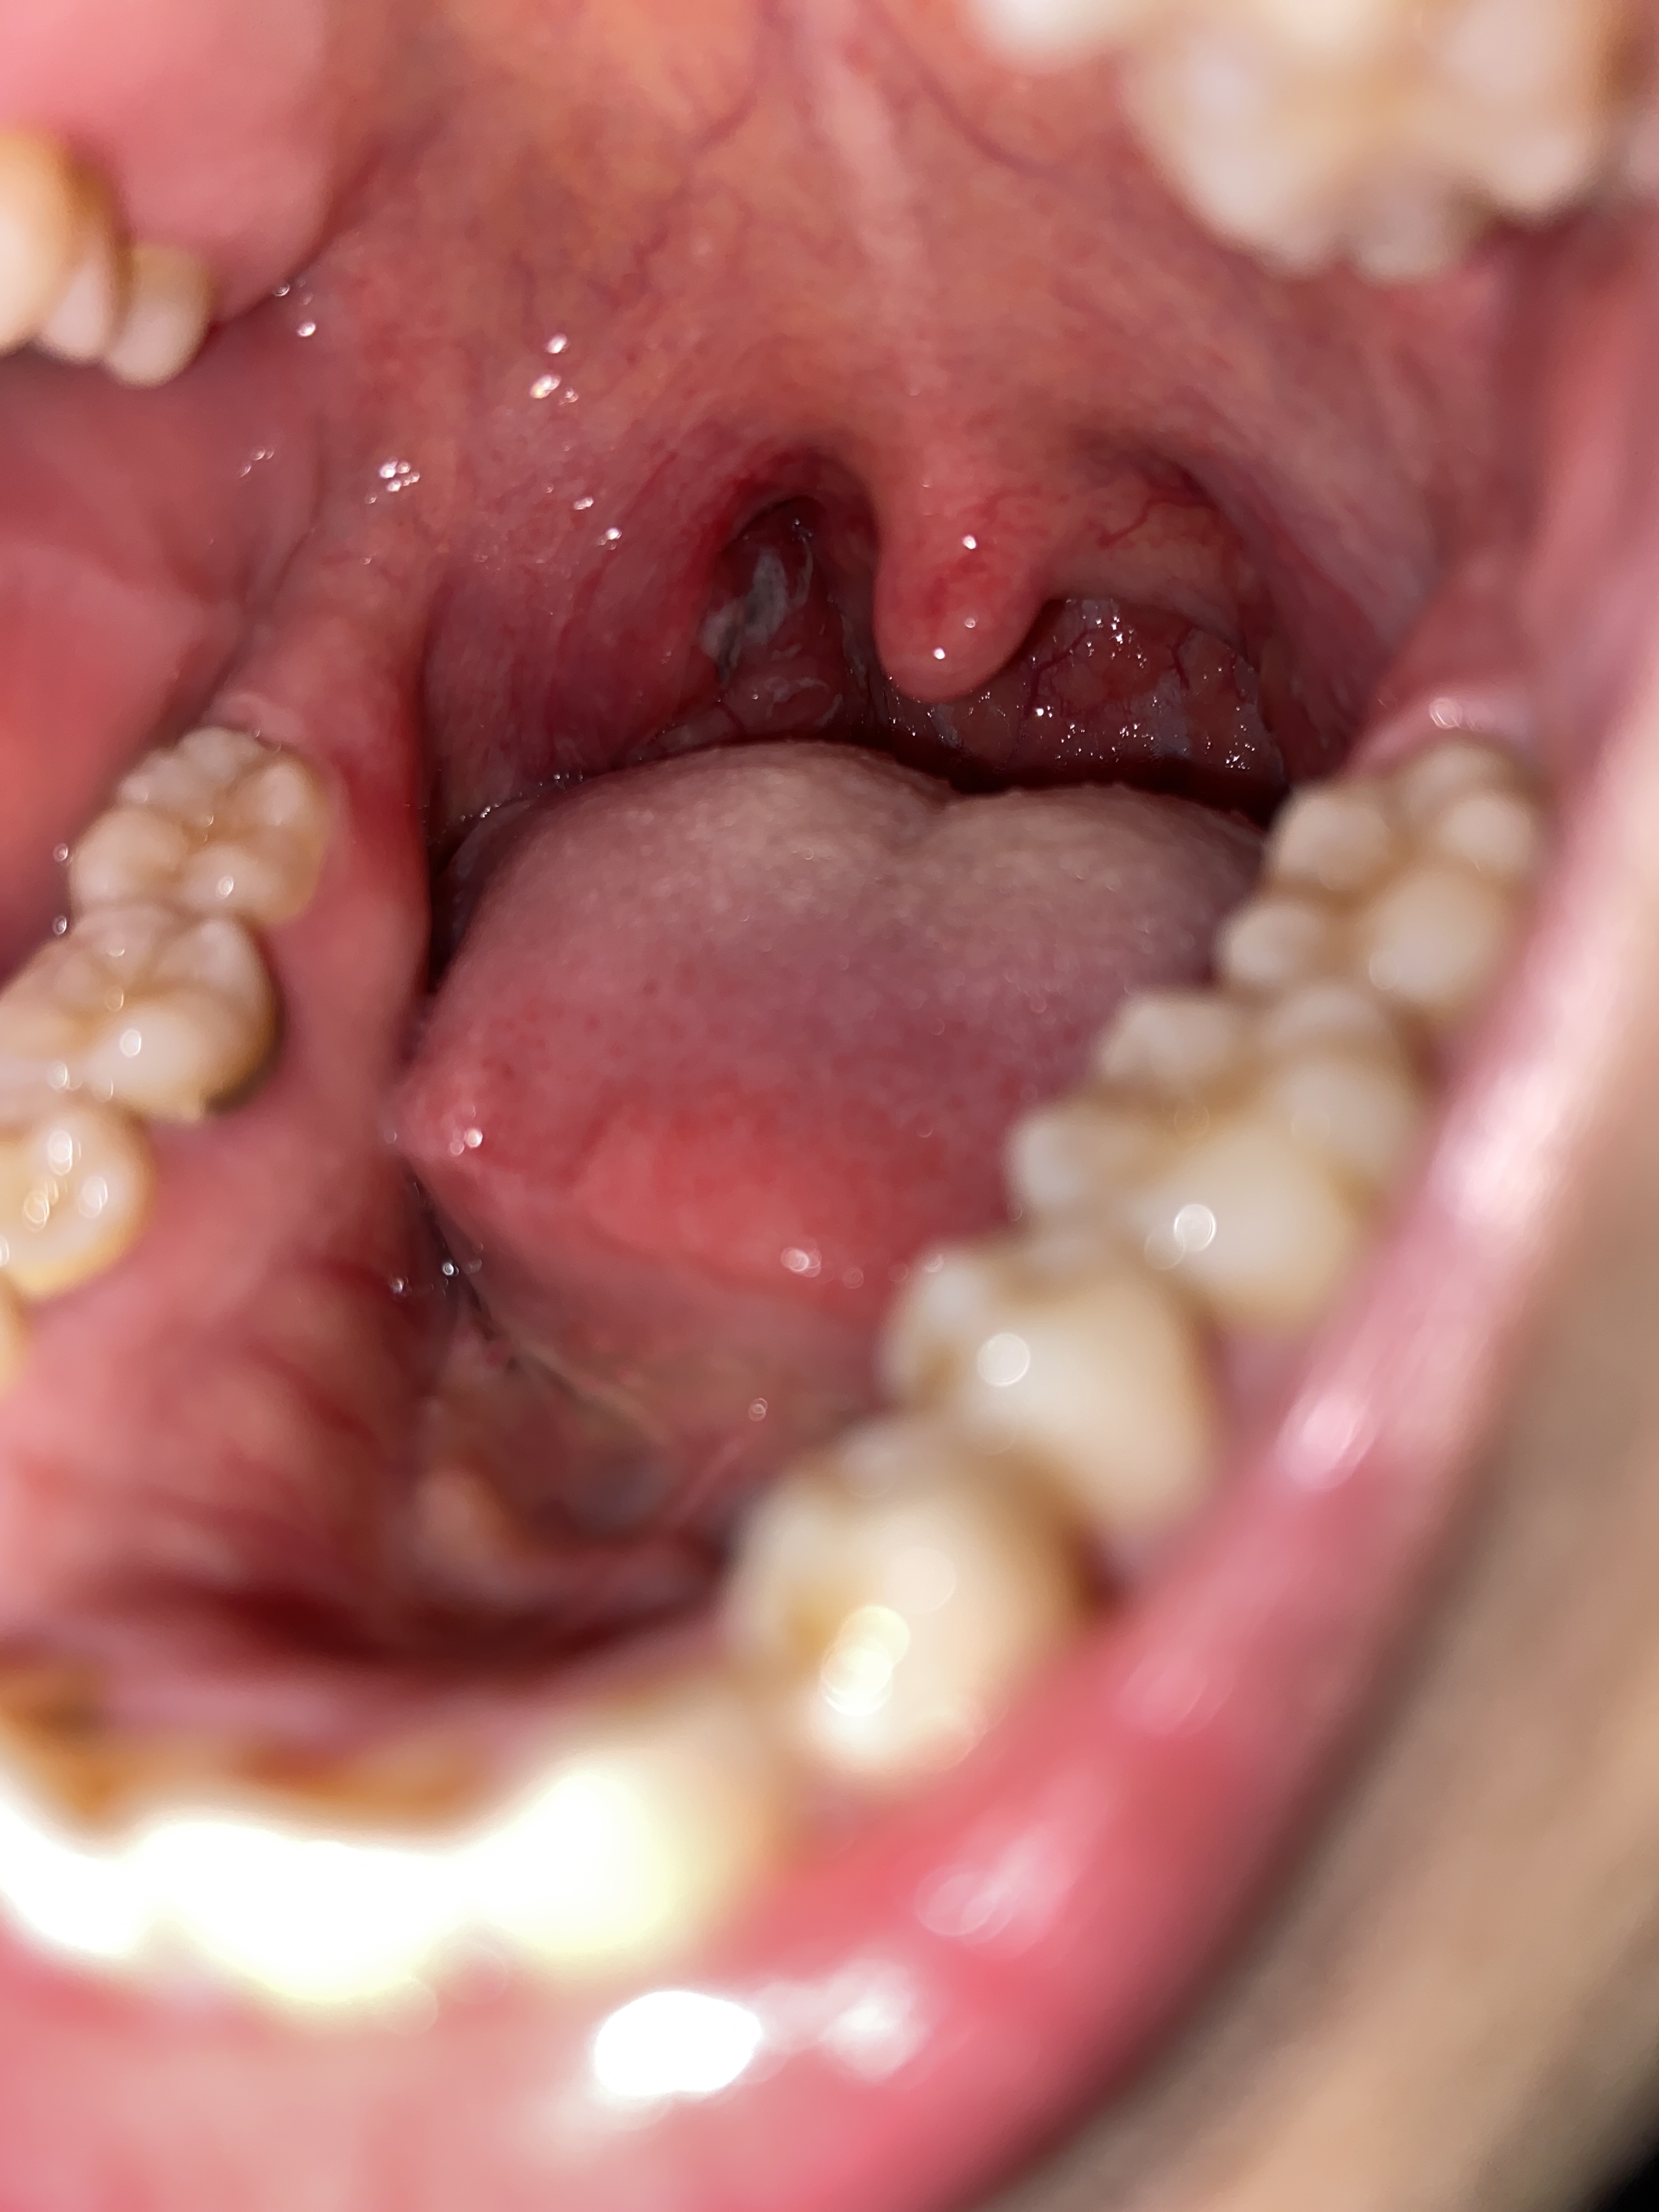

Bác sĩ ơi em đau họng xuất hiện mủ trắng.đi khám hồi sáng kết luận viêm amidan có mủ. Giờ soi đèn thấy mủ chuyển sang màu đen như này là sao ạ

Hình ảnh amydal hốc mủ. Vị trí đó em kiểm tra có hiện tượng vỡ mủ không